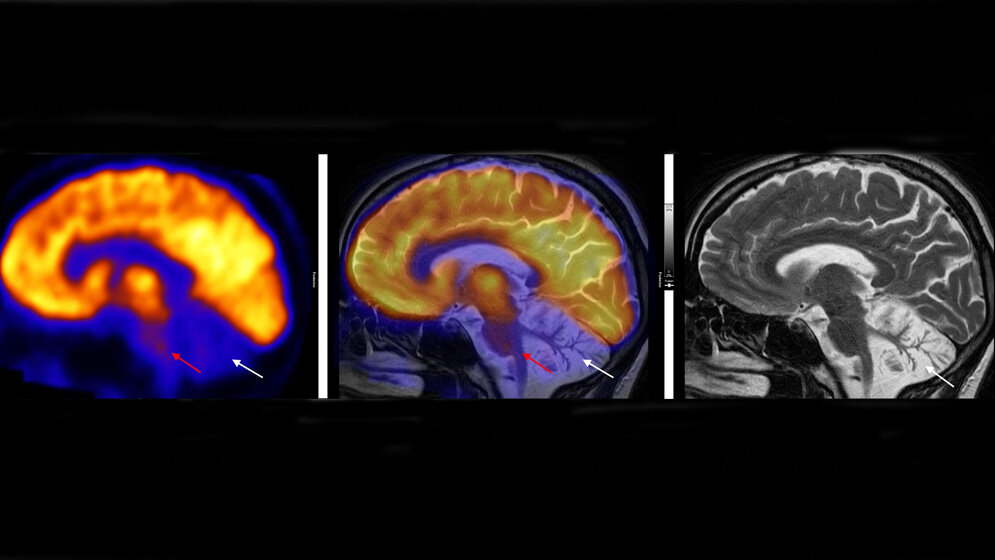

Stoffwechselaktivität des Gehirns (links: PET) und Struktur des Gehirns (rechts: MRT) sowie die Überlagerung beider Bilder (Mitte) bei einem Patienten mit SYNE1-Erkrankung.* Dr. Mona Mustafa, Klinik für Nuklearmedizin, LMU München

*Im Kleinhirn sind bereits viele Nervenzellen abgestorben (rechte Abbildung; weißer Pfeil). Die Stoffwechselaktivität ist nicht nur im Kleinhirn stark reduziert (weiße Pfeile), sondern auch im Hirnstamm (rote Pfeile, Hirnstamm leuchtet nicht mehr gelb). Das zeigt, dass die SYNE1-Ataxie viele verschiedene Gehirnbereiche betrifft.